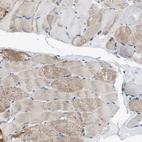

Immunohistochemistry analysis in human heart muscle and prostate tissues using HPA018174 antibody. Corresponding HHATL RNA-seq data are presented for the same tissues.